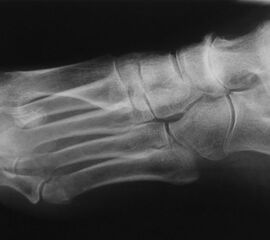

Alte Impressionsfraktur des Os cuboideum mit schweren Knorpelschäden.

Abbildung 9

Die isolierte Arthrose des Calcaneocuboidal-Gelenkes (CC-Gelenk) ist sehr selten. Mögliche Ursachen sind Traumen mit gewaltsamer Abduktion des Mittelfußes gegenüber dem Rückfuß. Der hierfür typische Unfallmechanismus wird meistens bei Zweiradfahrern vorgefunden 33. Impressionen der Gelenkfläche, Ausrisse des Processus anterior calcanei (Insertion des Ligamentum bifurcatum), sowie eine posttraumatische Instabilität des Gelenks können zu degenerative Veränderungen führen.